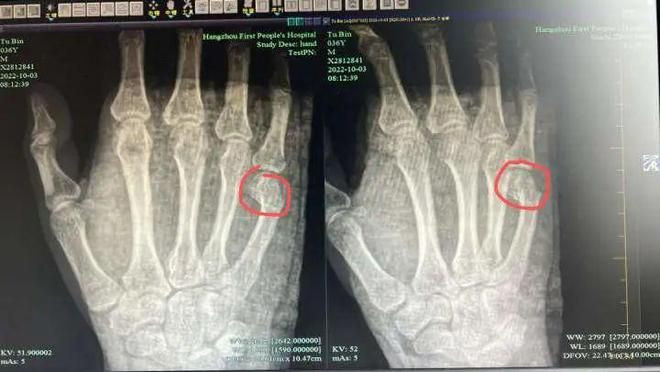

Kết quả chụp X-quang cho thấy đầu xa của xương ống thứ 5 ở tay phải của anh Ngô đã bị gãy, phần đầu bị gãy rõ ràng bị di lệch, cần phải nhập viện để thực hiện tiểu phẫu. Nghe thấy mình bị gãy xương bàn tay, anh miễn cưỡng nói: "Nhiều khi tức đến không nhịn được nữa. May mà cú đập này ở trên bàn, nếu trúng thằng bé thì phiền phức lớn".